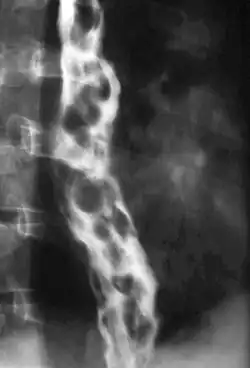

Nach Aussehen und Eigenschaften während der Endoskopie kann eine klinische Stadieneinteilung in Grad I - IV erfolgen:

- Stadium I: Es liegen Erweiterungen der submukösen Venen vor, die jedoch nach Luftinsufflation durch das Endoskop verstreichen.

- Stadium II: Es bestehen einzelne in das Lumen des Ösophagus hervorragende Varizen, die auch bei Luftinsufflation bestehen bleiben.

- Stadium III: Das Lumen des Ösophagus ist durch hervorragende Varizenstränge eingeengt. Als Zeichen einer Epithelschädigung (Erosion) können rötliche Flecken ("cherry spots") auf der Schleimhaut bestehen.

- Stadium IV: Die Varizenstränge haben das Ösophaguslumen verlegt, es bestehen in der Regel zahlreiche Erosionen der Schleimhaut.